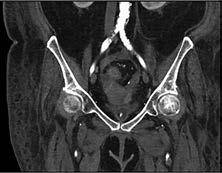

Kardiale Bildgebung

Kardio-CT: Auch im Bereich der kardialen Gefäßdarstellung ist nach wie vor die invasive Koronarangiographie in der Diagnose der koronaren Herzkrankheit der aktuelle Goldstandard. Jedoch hat die koronare CTA aufgrund ihrer hohen zeitlichen und räumlichen Auflösung einen wachsenden Stellenwert bezüglich der Diagnostik einer bestehenden koronaren Herzerkrankung, aber auch hinsichtlich eines sicheren Ausschlusses einer bestehenden revaskularisationsbedürftigen Stenose. Zudem vermeidet die CTA die mit einem invasiven Verfahren verbundenen Risiken und bietet darüber hinaus eine schnellere und möglicherweise kostengünstigere Möglichkeit zur Beurteilung von Patienten mit mittlerem Risiko für eine koronare Herzerkrankung. Die nichtinvasive anatomische Visualisierung mittels koronarer CTA ermöglicht eine direkte Darstellung des Ausmaßes und der Lage von Koronararteriosklerose und Koronarstenosen (Abb. 4).

Des Weiteren bietet die kontrastfreie CTA die Möglichkeit zur Berechnung eines Koronararterienkalk-Scores, wobei es sich um ein flächendeckend verfügbares, konsistentes und reproduzierbares Verfahren zur Bewertung des Risikos schwerer kardiovaskulärer Folgen handelt, das insbesondere bei asymptomatischen Personen für die Planung von Primärpräventionsmaßnahmen angewendet wird. Moderne CT-Untersuchungen (MultiDetektor CT, MDCT) können mit einer Gesamtdauer von 10 – 15 Minuten bei einer Strahlenbelastung von etwa 1 mSv durchgeführt werden.

Abbildung 4: Mittels CT-Angiographie des Herzens nachgewiesene Stenose des Ramus interventricularis anterior (Pfeil).